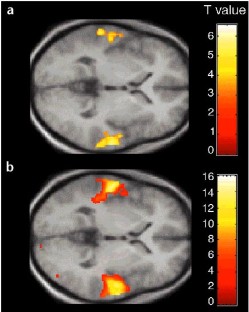

We measured the neural activity associated with the temporal structure of sound in the human auditory pathway from cochlear nucleus to cortex. The temporal structure includes regularities at the millisecond level and pitch sequences at the hundreds-of-milliseconds level. Functional magnetic resonance imaging (fMRI) of the whole brain with cardiac triggering allowed simultaneous observation of activity in the brainstem, thalamus and cerebrum. This work shows that the process of recoding temporal patterns into a more stable form begins as early as the cochlear nucleus and continues up to auditory cortex.

Griffiths, T., Uppenkamp, S., Johnsrude, I. et al. Encoding of the temporal regularity of sound in the human brainstem. Nat Neurosci 4, 633–637 (2001). https://doi.org/10.1038/88459